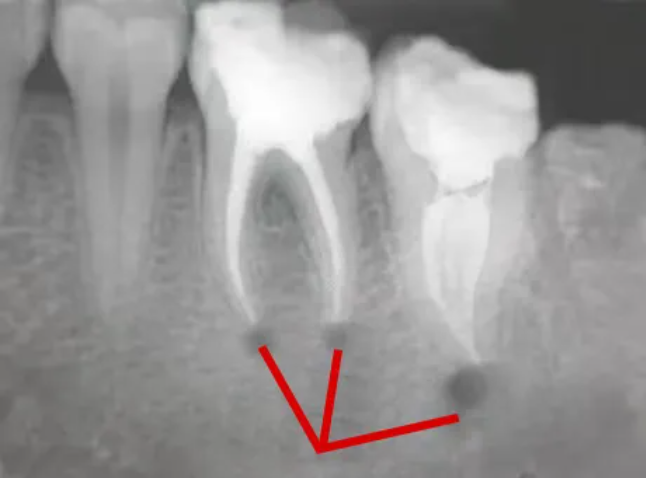

🔎根尖炎症

△根尖那里有黑色的阴影,一般说明牙根尖有炎症病变,这种多为根尖炎。